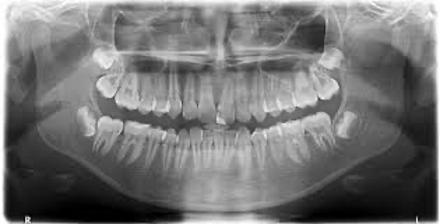

Orthopantomogramm (OPT)

Bei einem Orthopantomogramm (Panoramaschichtaufnahme),wird der gesamte Ober- und Unterkiefer mit allen Knochen- und Zahnstrukturen abgebildet.

Hierfür wird der Patient in ein hochmodernes Röntgengerät platziert. Das Gerät dreht sich in wenigen Sekunden um den Kopf des Patienten und liefert in Echtzeit digitale Bilder, die zum Planungserfolg von chirurgischen Therapien, wie zum Beispiel chirurgischen Weisheitszahnentfernungen oder Implantationen, zwingend notwendig sind.